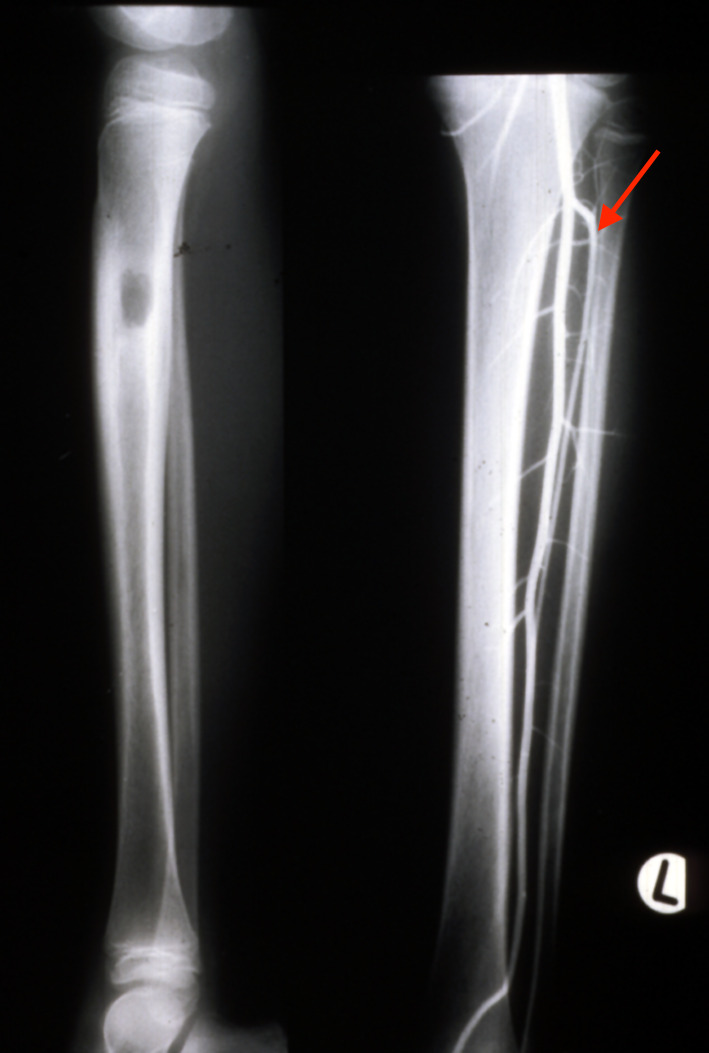

A two-stage transfer of the ipsilateral fibula was then attempted by our orthopaedic team, based on a muscle pedicle and fixed to the tibia with screws. Unfortunately, the bone failed to knit at the upper end. It developed a pseudarthrosis and the patient was left with a flail leg (Figure 2). Amputation was recommended but ‘if a skin flap can be transferred successfully with microsurgery why not bone, and which one?’

In 1983, a nine-year-old girl presented with a Ewing’s tumour of the right tibial diaphysis (Figure 10 left). She was treated initially with chemotherapy for 12 months with a good result. Segmental resection of the tibia was contemplated and we were invited by Ian Torode and Bob Dickens to consider a fibula reconstruction at the Royal Children’s Hospital Melbourne. Preoperative angiography however, revealed a single peronea magna supplying the foot in the other donor leg. The anterior tibial artery was diminutive (Figure 10 right) but was considered to be of a sufficient size to nourish the fibula transplant.